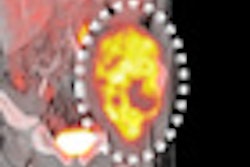

Finally, an FDG-PET brain scan was acquired to detect metabolic abnormalities in the brain that might signal Alzheimer's disease. FDG-PET's glucose metabolism slows when the brain is functioning abnormally, resulting in lower levels of FDG uptake.

"We are inferring that when there is this lowered glucose metabolism in Alzheimer's patients, and even before mild cognitive impairment, the disruption of neural networks is already well under way and that's why we are seeing this global effect," Landau said.

| FDG-PET images show reduced glucose metabolism in temporal and parietal regions in patients with MCI and Alzheimer's disease. Images courtesy of Suzanne Baker, PhD; William Jagust, MD; and Susan Landau, PhD. |